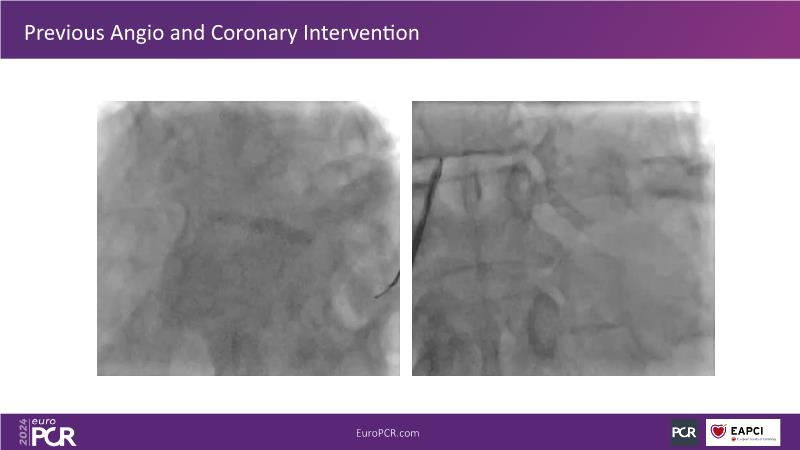

Physiology guided post-DCB treatment to safely limit stenting. Validation in complex clinical settings with the optical Optowire III pressure guidewire

Follow this session to discover how accurate resting index can inform decision-making for DCB in CTO patients and understand the role of physiology in a new PCI workflow for complex MVD. Thus, you will learn about a DCB intention-to-treat strategy guided by post-PCI coronary physiology in complex lesions, review new procedural techniques and workflows from real-world cases, and explore the pros and cons of this novel approach.

- To review new procedural technique and workflow from real world patient cases